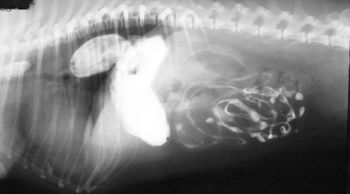

A contrast enema study helped clinicians detect an intestinal stricture in this exotic pet. See how this diagnostic step can help your reptile patients with similar signs.

Add a little contrast to help you find your diagnosis.

Examine the imaging results to help solve this pug's problem.